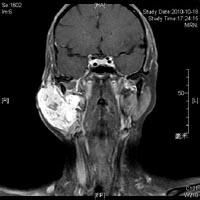

面部血管瘤血管瘤是指發生於血管組織的一種良性腫瘤,是由於血管組織的錯構,瘤樣增生而形成。分為原發性和繼發性兩種,其中原發性占75%,繼發性25%左右。繼發性多數在嬰兒期出現,少數在成年期發現,病因尚不清楚。原發性即先天性胎生性是由人體胚胎期血管網增生而形成,出生時即有,血管瘤較小時可無症狀。血管瘤可發生於身體各部位,長在顏面及四肢暴露部位,可以影響容貌。不同程度地壓迫、破壞周圍組織器官的功能和形態,影響人體的生長發育。有的可以反覆出血、感染,極少數人會產生惡變,甚至危及生命。